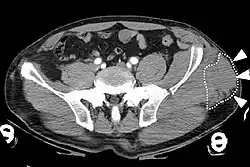

Computed tomography

Computed tomography (CT) is important in settings of an emergency or when magnetic resonance imaging is not available.[8] CT will show the presence of a Morel-Lavallée lesion and whether fluid is present.[7] The use of contrast can also help determine if fluid present in a lesion is due to active bleeding.[8]

Fluid in a Morel-Lavallée lesion can be removed by percutaneous aspiration.[8] Aspiration is a technique where the fluid is removed with a needle and suction. Ultrasound or CT imaging can be used to visualize the area beneath the skin when performing the aspiration.[8] Compression bandages can be applied after aspiration to help with healing.[8] Despite aspiration, fluid can recur.[6] Catheters or surgical drains can be left in the space so that any new fluid accumulation after aspiration can drain outside of the body.[7]